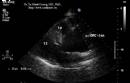

Nghiên cứu chức năng tâm trương thất trái và thất phải bằng siêu âm Doppler tim (Luận án Tiến sỹ Y học của TS. Tạ Mạnh Cường - Full text)